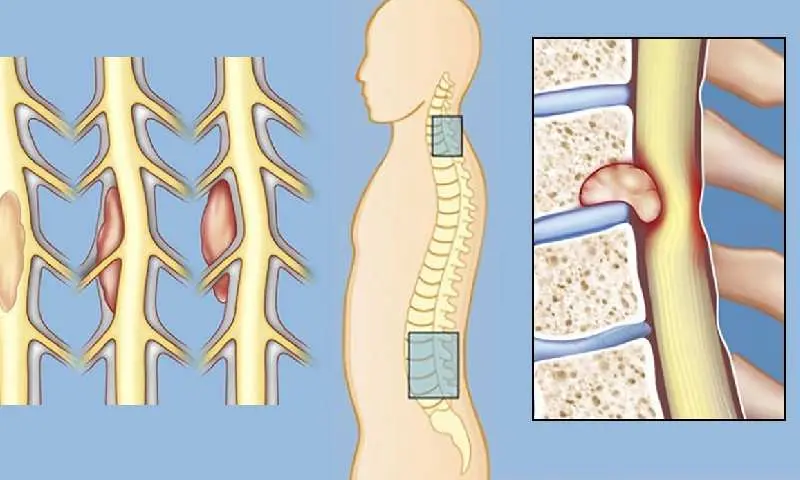

0 تا 100 تومورهای نخاعی

تایید شده توسط پزشکان متخصص ایزی مد محتوای این مقاله صرفا برای افزایش آگاهی شماست. قبل از هرگونه اقدام با پزشکان ایزی مد مشورت کنید عنوان موضوعات این صفحه تومور نخاعی خوشخیم از تومورهای مهم است که در ناحیه ستون فقرات تشکیل میشود. این نوع…